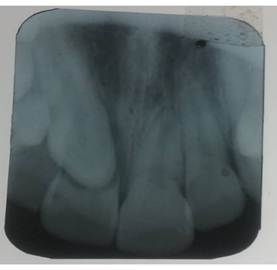

Radiographic findings:

A periapical radiograph of the upper anterior region was requested, which revealed root resorption of tooth 11 (Figure 1). This resorption was attributed to the presence of the impacted canine (13) dental follicle in an ectopic position, displacing and affecting the incisor root.

Figure 1. Periapical radiograph of the upper anterior sector.

In the patient presented, the periapical radiograph confirmed the loss of root continuity of the central incisor (11), a finding that proved crucial in treatment planning.